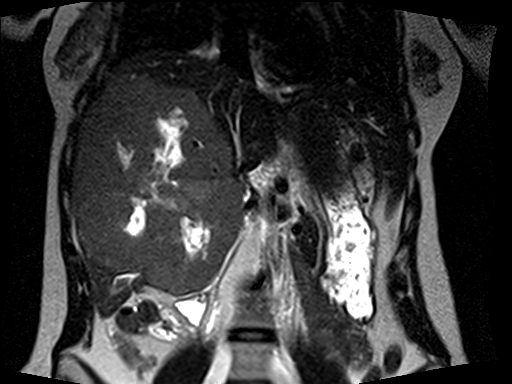

We spoke for ten or fifteen minutes and then I performed an abdominal examination. With her lying supine on the examination room table, it was possible to palpate a mass originating in her upper abdomen and extending well below her umbilicus.  The mass was not tender but was firm.  After completing the evaluation, I walked out and loaded the disk with her MRI scans onto my computer workstation.  When I opened the abdominal images, I let out a low whistle.  Quickly, every physician, resident, nurse, and student in clinic was clustered around the computer screen.  A couple of representative images explaining their interest and excitement are seen in the two images below.

Almost the entire right lobe and the medial segment of the left lobe of her liver was occupied by an enormous tumor. There were areas of necrosis, or dead tissue, and other regions demonstrating recent hemorrhage, or bleeding into this tumor.  The characteristics and MRI appearance were all consistent with a benign type of liver tumor called a giant cavernous hemangioma. The term giant was an understatement in this young lady. Hemangiomas are abnormal, but not malignant, spongy collections of blood vessels which can occur in many solid organs in the body. A familiar type of hemangioma is one arising in the skin (which is a large solid organ), known by the common vernacular name as a port wine stain.

This tumor was massive and clearly causing symptoms, so even though benign, I recommended surgical removal. I knew the operation would be a hepatobiliary surgery tour de force because the right and middle hepatic veins were compressed and the tumor abutted and bowed the main, left, and right portal veins.